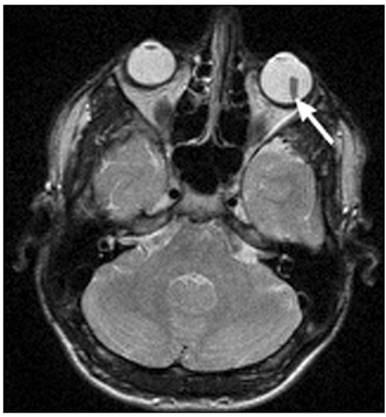

МРТ: возможна визуализация рентгенонеконтрастных

инородных тел (см. рис. 8).

Рис. 8. МР-томограмма. Пластмассовое инородное

тело левого глазного яблока (стрелка)